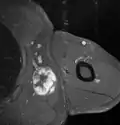

Medical ultrasonography and magnetic resonance imaging (MRI) of liposarcomas are helpful and often essential in determining their extent, surgical accessibility, and relationship to any observed organ dysfunctions. Since ultrasonography is usually unable to distinguish a liposarcoma from a benign lipoma, MRI is the initial imaging of choice to provide evidence relative to making this distinction.[67]

In myxoid liposarcoma, it shows low signal intensity mass with high signal intensity foci on T1-weighted MRI images. The mass shows high signal intensity on T2-weighted images. This is because it contains predominantly mucoid substance (accounts for low signal intensity on T1) and small amount of mature fat (accounts for high signal intensity on T1).[68] The mass is well-defined, lobulated, multiloculated, or oval in shape without any infiltration into surrounding structures.[68]

Fig. 7 MRI of myxoid liposarcoma of high grade, in the left axillary region of 40-year-old man, highlighted by its white color, in this horizontal section of the tumor.